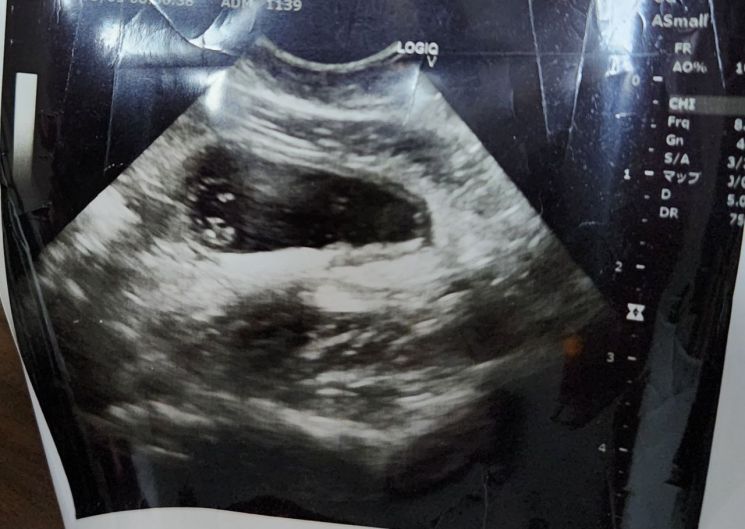

[파이낸셜뉴스] 일본에서 '태아 초음파' 중고거래가 활성화 되고 있는 가운데, 유명 중고거래 플랫폼이 판매를 금지하기로 했다.

27일 일본 니혼게이자이 신문에 따르면 중고거래 플랫폼 메르카리는 다음달 1일부터 태아 초음파 사진 판매를 금지한다.

이번 조치는 태아 초음파가 '임신 사기'등에 악용될 수 있다는 우려가 커지면서 나왔다. 일본에선 태아 초음파 사진을 구매한 뒤 남성에게 '임신했다'고 속여 임신중절 수술비 등을 받아내는 사기 행각이 논란이 됐다. 거래 가격은 3만~10만원 안팎으로 알려진다.